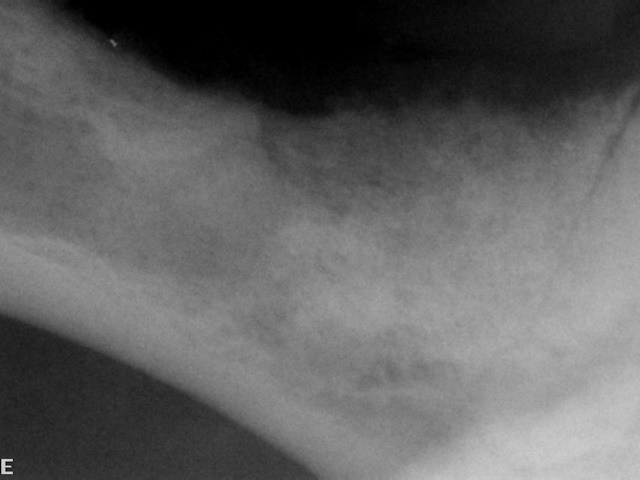

On dental radiograph it was hard to see the cyst, since it was not too big. But a periapical lesion is seen around the palatal root of first molar tooth.